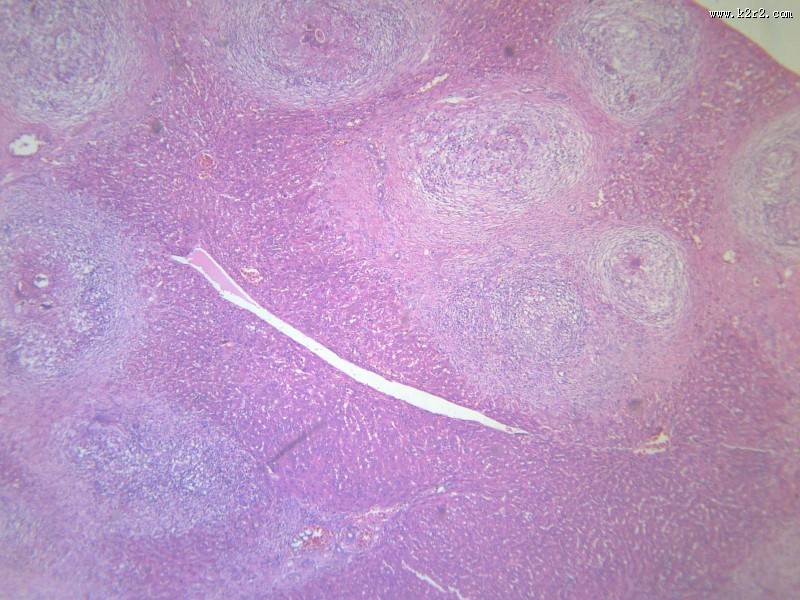

首页 > 其他类别 > 虫卵肉芽肿(12张) > 虫卵肉芽肿 第1张

虫卵肉芽肿 - 第1张